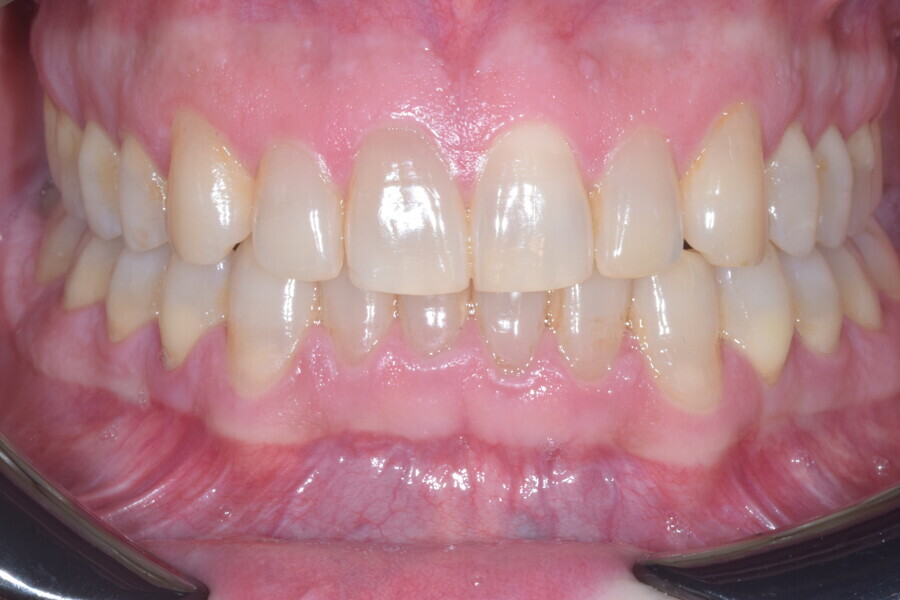

At the end of the treatment, Class I canine and molar relationships were obtained, maxillary incisor inclination was slightly increased (Ui–FH = 112°), mandibular incisor inclination (IMPA = 97.09°) was fully corrected by means of proclination and the divergency was slightly increased (SN–GoGn = 27°) because of the relative posterior extrusion and use of Class II elastics—a small variation (1°), which is interesting considering the age of the patient (Figs. 25–35). A balanced smile arc was obtained with an ideal relationship between the maxillary incisors and lower lip, and torque control of the lateral and posterior segments generated a broader smile.

At the one-year follow-up in retention (Vivera retainers with bite ramps, Align Technology), the result was stable and intercuspation was improved (Figs. 38–42).